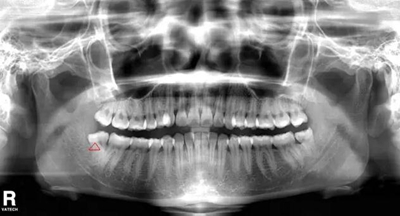

智齒水平阻生(長橫過來了),影響前面牙齒或者致前面牙齒擁擠不齊

1.jpg